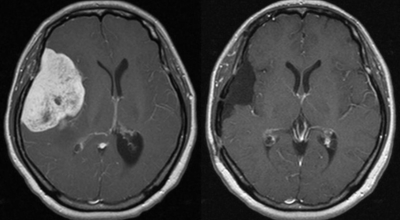

뇌종양이 악성인 경우, 빨리 자라는 특성이 있기 때문에 수술적으로 절제가 필요할 수 있습니다. 하지만 수술로 종양이 완벽하게 제거가 어려운 경우, 수술 후에 방사선 치료와 항암치료를 추가적으로 시행되어요. 요즘 들어서 뇌조직의 훼손을 최소화하고 수술 흉터가 거의 남지 않는 방법으로 하는 치료인 감마나이프 방사선 수술이 있답니다. 이 방사선 수술은 전신 마취와 피부 절개가 필요 없으며, 합병증이나 후유증이 적은 것으로 알려져 있답니다.

종양의 부위가 너무 커서 다른 방법을 활용하기 어렵거나 신경학적으로 생기는 증상이 너무 심하다고 판단이 될 경우에 활용할 수 있답니다. 하지만 다발성 병변으로 발생한 종양이거나 면역력이 많이 떨어져 있는 등 전신이 쇠약한 환자의 경우, 신중하게 생각해보아야 해요.